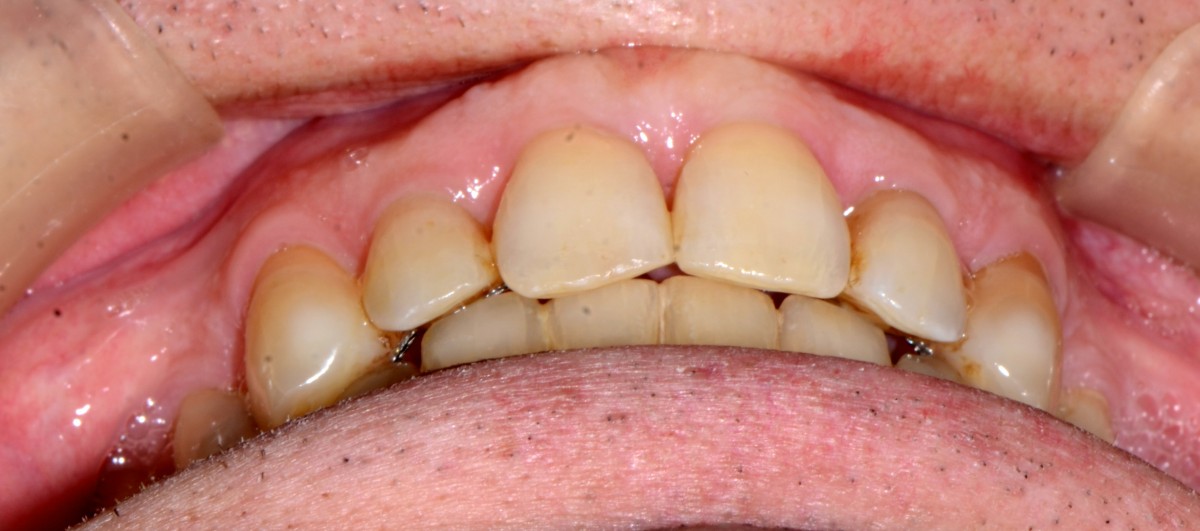

In this figure, patient during the Invisalign treatment. Note the perfect fit of the aligners due to correct planning and imple- mentation of biomechanics rules together with very com- pliant patient (figs. 10, 11).

It is not every case that we con- sider a “life change”... this treatment for this patient was so important and the change we have achieved in his smile, function and aesthetics is dra- matic not to speak on the fact that we have probably saved his teeth from further destraction (figs. 12-16).